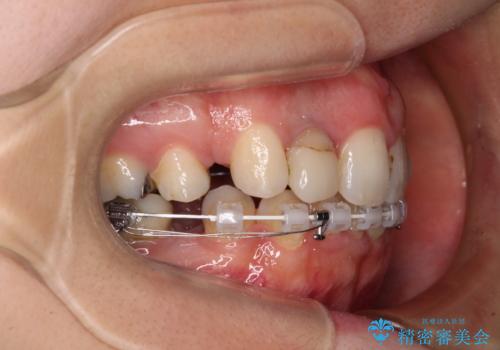

目立たないハーフリンガル矯正を希望され、裏側装置はどうしても清掃性が低下し、むし歯発生のリスクが高まるため、矯正治療前にしっかりとむし歯治療を行い、矯正治療後にセラミックによる補綴治療を行うこととしました。

抜歯したスペースがなかなか閉じず、治療に時間はかかりましたが、術前術後のむし歯治療と合わせて3年10ヶ月で治療を終えることができました。